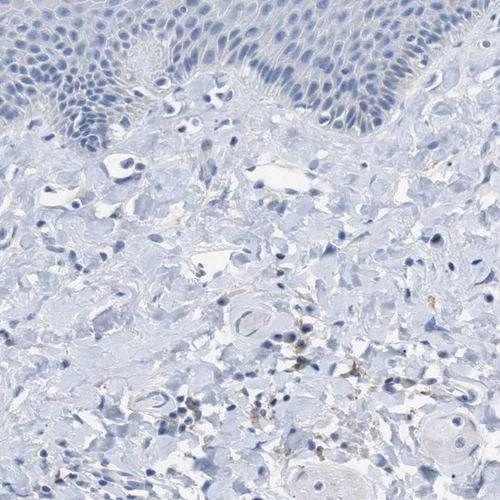

Immunohistochemical staining of human spleen shows weak membranous positivity in cells in red pulp.